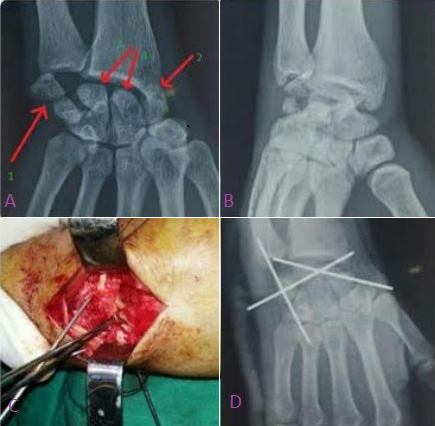

Nous rapportons le cas d’un jeune homme de 21 ans victime d’une chute de sa moto sur la main droite occasionnant une fracture luxation trans-scapho-rétro-lunaire associée à une fracture verticale de pyramidal (A et B). A j+2 lepatient a bénéficié d’une réduction sanglante (C) des os du carpe désorganisés avec ostéosynthèse du scaphoïde et du pyramidal (D). La fracture-luxation péri lunaireest une lésion rare constituant 5 % à 10 % des lésions traumatiques du poignet, souvent sous-diagnostiquée et nécessite un traumatisme en hyperflexion palmaire, l'association d’une luxation-fracture de pyramidal est encore plus rare. Les luxations péri-lunaires du carpe peuvent laisser des séquelles fonctionnelles graves si elles ne sont pas diagnostiquées rapidement après le traumatisme. Le diagnostic est très aisé et un simple examen radiologique permet de poser le diagnostic.